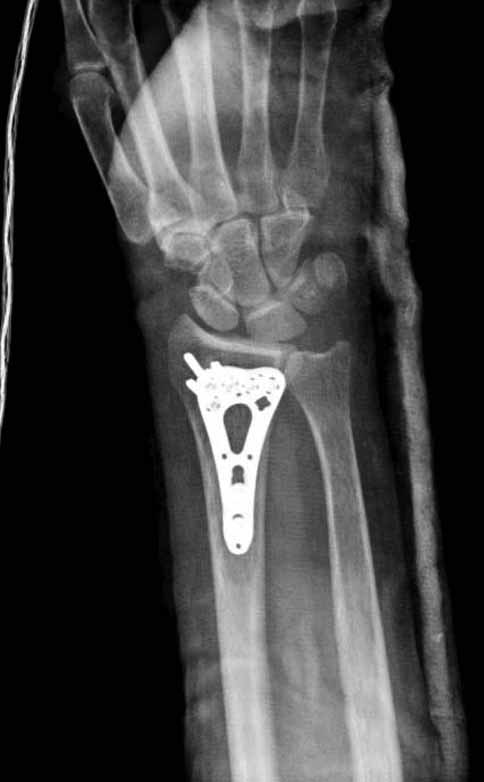

Стандартная волярная пластина для дистального отдела лучевой кости (Synthes; Stryker; Chm; Рыбинск;ЦИТО;Остеомед,De puy; Intercus GmbH)

Лучше с угловой стабильностью.

Хорошие волярные (ладонные) пластины предмоделированны и репозиция происходит на пластине.

Стандартный ладонный (волярный) доступ.

К сожалению аналогичную картинку у оперированной больной не нашел (хотя и копировал- бардак в компе). Там поставили волярную пластинку ChM, которую закупила больница.